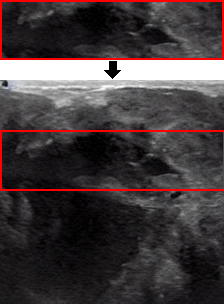

To gain further insights, we examined attacked examples from the training set, focusing on images that the classifier identifies with high confidence. Figure 6 presents malignant cases from the BUSI training set alongside their attacked versions generated by Diff-PGD and our method, P2P. As illustrated, the Diff-PGD attack introduces a noticeable noise pattern, while our method produces images that closely resemble the originals. Interestingly, additional examples reveal that Diff-PGD’s image quality deteriorates as the classifier’s confidence increases. While attack experiments are generally performed on validation sets, we analyzed training set images here to understand the performance of different attack models in varied scenarios.

Refer to caption a) Original Refer to caption b) Diff-PGD Refer to caption c) P2P

Figure 6: Attack examples of a malignant image of Dataset BUSI from Diff-PGD and P2P with ResNet34 as a classifier.